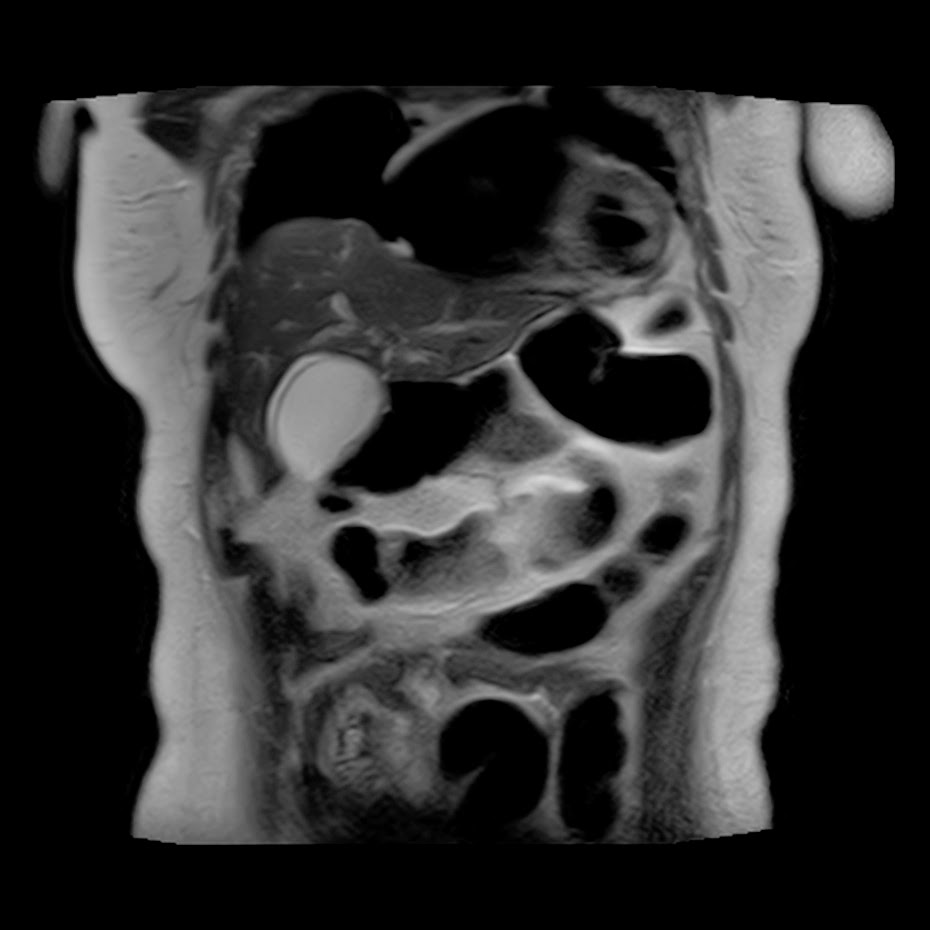

Caso interesante #5

Paciente con dolor en hipocondrio derecho.